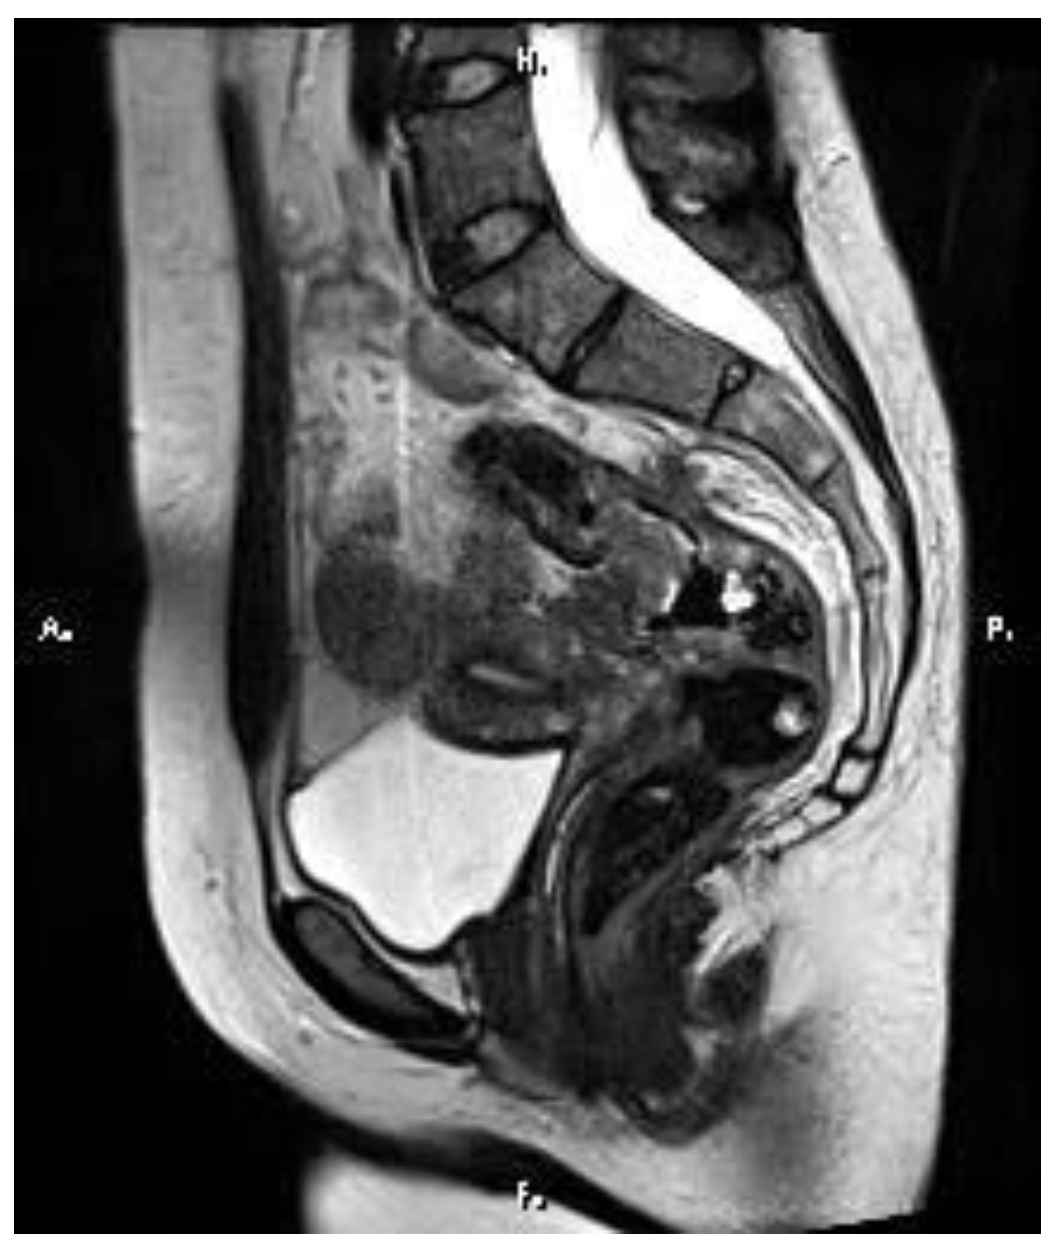

2. Case Report